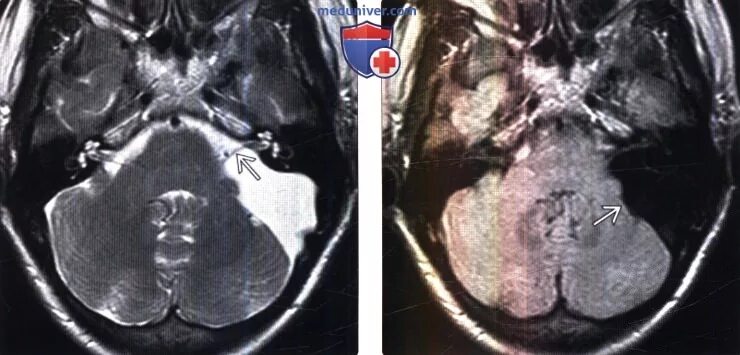

Мрт головного мозга мосто мозжечкового угла